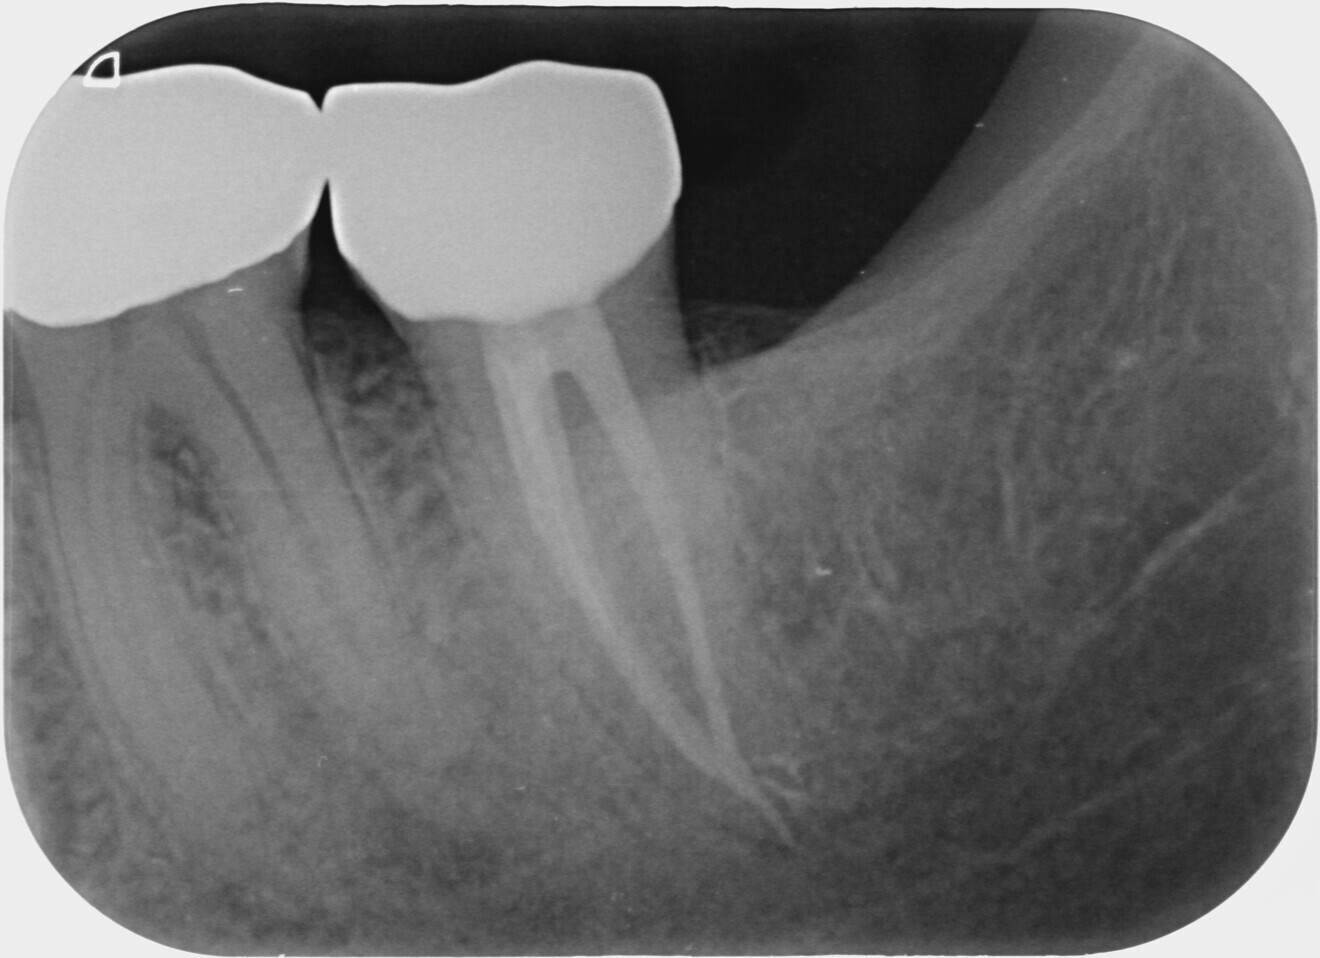

During a 30-second resting phase, the irrigant within the pulp chamber appeared to become cloudy. Number 10 files were placed in all the three canals until resistance was met, and all were restricted from passing 18 mm. A working length radiograph was taken (Fig. 2), and it showed that the files in the mesial canals had reached a point of constriction or obstruction which would not allow further access towards the apex. After a further five cycles of laser-assisted irrigation with 17% EDTA with a 30-second resting time and recapitulation with #10 and 15 files, the instruments were able to reach the apex at 22 mm in the distal canal and 21 mm in the mesiobuccal and mesiolingual canals (Fig. 3). This showed that the irrigant had successfully penetrated the canal system and dissolved the blockage that had prevented initial access to the apical segment. After the canals had been prepared with rotary files, the final irrigation protocol was done, initially allowing more cloudy liquid to float to the surface. At the completion of laser-assisted irrigation, the canals were dried with paper points, and no bleeding was observed.

Fig. 3.